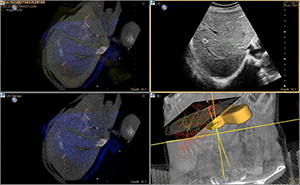

今回のモデルチェンジにより,「EPIQ Evolution 1.0」は,さらなる画質と操作性の向上に加え,新機能の搭載が可能となった。新たに搭載される新技術Auto Registration(オート・レジストレーション)*2は,現場の先生方が待ち望んでいた,“真のフュージョン機能”である。従来のマニュアル法と違い,指紋認証と同様のアルゴリズムを用いることで,自動(オート)でCT/MRI/PETと超音波のフュージョンを可能にした。これにより,超音波診断装置と超音波診断装置以外の装置(CT/MRI/PET 装置)の画像のコラボレーションが簡単かつ高精度で可能になり,日常臨床で身近に活用できるツールとなった。様々な領域(肝臓や腎臓などの腹部臓器,前立腺,脳血管など)における,超音波ガイド下治療や治療後評価への活用が期待される。

Auto Registration: 症例画像 |

新技術Auto Registrationは,従来の「点」や「面」で位置合わせする方法ではなく,「3次元」ボリュームデータを用いて自動フュージョンする方法。血管の立体構造をもとに位置合わせをするVessel Base(指紋認証)と,肝表面の立体構造をもとに位置合わせをするSurface Base(顔認証)の2種類の方法が選択可能である。

・Vessel Base(指紋認証):肝内血管の立体構造で位置合わせをする方法。肝内血管の走行は,指紋のように人それぞれ異なる。3D-CT画像と3D超音波画像から血管の立体構造を抽出し同期することで,高い精度でフュージョンすることが可能。

・Surface Base(顔認証): 肝表面の形状で位置合わせをする方法。顔認証のように全体的な位置合わせが可能。